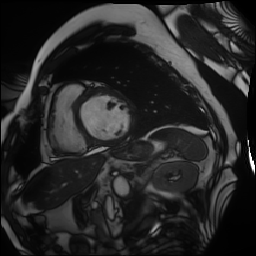

ACDC dataset [2] is a four-class segmentation benchmark (background, right ventricle, left ventricle, myocardium) comprising 100 patient scans. Following the setup in BCP and related works, we allocate 70 scans for training (1,312 images), 10 for validation, and 20 for testing. For semi-supervised scenarios, we explore 5% and 10% splits of the training data, equivalent to 68 and 136 images respectively, to align with prior semi-supervised methodologies and simulate low-data conditions.

Synthetic Data: For our experiments, high-fidelity synthetic images are generated using StyleGAN2-ADA [16] as described in Section 3.1.2. The model is trained exclusively on the limited percentage of real labeled data available for each dataset (e.g., 5% or 10%). For instance, when using 10% labeled data (136 images for ACDC or 56 for FIVES), StyleGAN2-ADA is trained solely on these specific images. Figure 3 shows random synthetic samples generated for both ACDC and FIVES datasets at 5% and 10% labeled data splits.

To augment the limited real labeled data, high-fidelity synthetic images are generated using StyleGAN2-ADA [16]. The model’s Adaptive Discriminator Augmentation (ADA) mechanism dynamically adjusts augmentation probability to prevent discriminator overfitting on limited training samples, enabling realistic and diverse image generation even from minimal input. Figure 3 presents random selected synthetic images for the ACDC and FIVES datasets at the 5% and 10% labeled data splits.

We train StyleGAN2-ADA on the aforementioned 5% or 10% real labeled data. The quantity of generated synthetic images matches the remaining proportion of the full dataset (e.g., 90% or 95%), effectively serving as the unlabeled data input for the SRA-Seg framework.